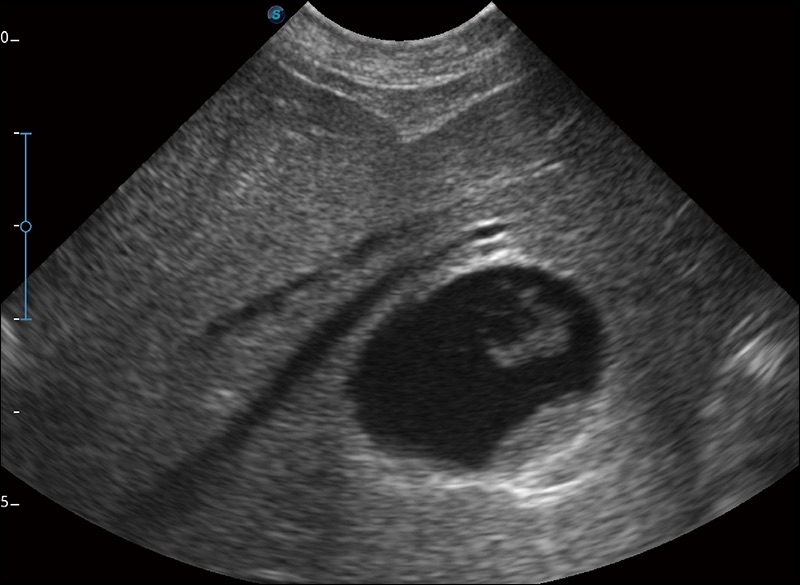

扩展成像

支持线阵和凸阵探头,一键操作即可获得更宽的图像视野

实时宽景成像

可实时观察感兴趣区域和病变位置

穿刺针增强

高清显示穿刺进针情况